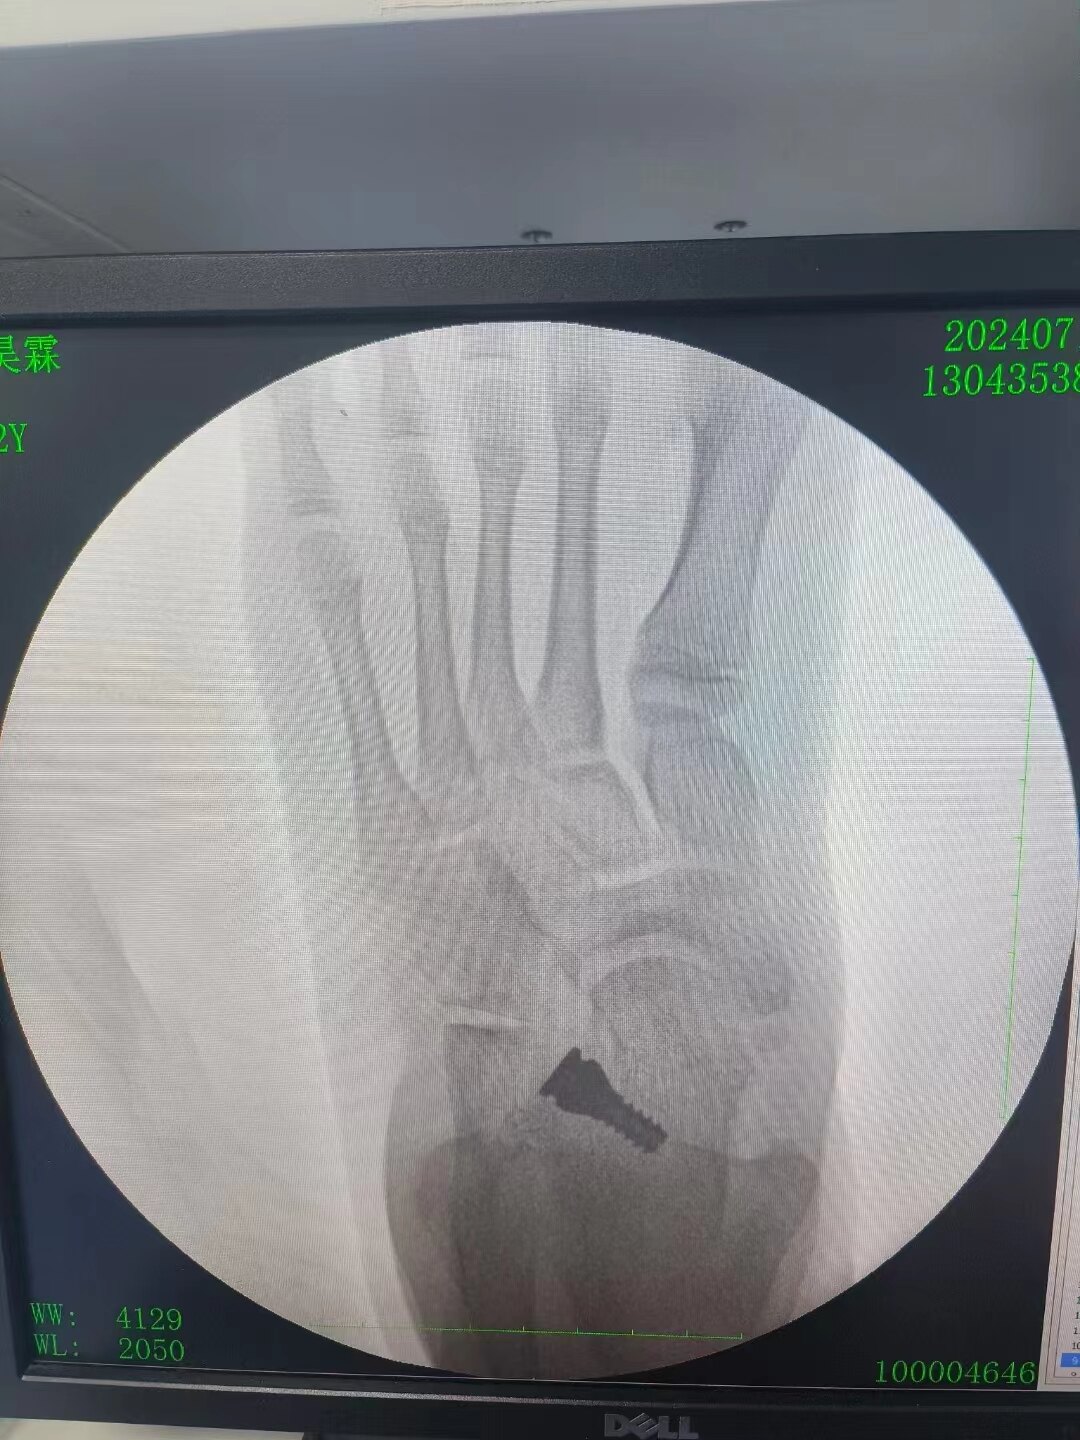

刚出生的婴儿是没有足弓的,随着生长发育,足弓逐渐出现,有研究发现18个月婴幼儿97%是平足,3岁儿童中平足为54%,6岁降为26%,成人中平足占15-23%,一般认为正常足弓形成于8岁左右(6-10岁之间)。男孩发病多于女孩,肥胖儿童发病率高于正常儿童。平足大致可以分为先天性和后天性两类。先天性平足病因不明,可有遗传因素比如:先天性垂直距骨、跗骨联合、副舟骨等。后天性平足病因包括:外伤性、神经肌肉源性、代谢性骨病(如糖尿病、类风湿关节炎等)、肥胖、增龄性退变等。 那么青少年平足症如何治疗呢?扁平足的治疗主要有减少负重、理疗、矫正鞋垫/鞋和手术治疗,或几种方法的联合使用。减少负重包括减轻体重、减少背负重物、减少行走站立或跑跳运动,对于一些轻症患者往往就已经能够缓解症状。理疗和功能锻炼对各个阶段的患者都有作用,方式包括足内在肌训练(缩足运动、毛巾卷曲运动、足趾拾弹珠运动、足趾屈伸/分离运动);足外在肌训练(胫后肌向心/离心抗阻运动、小腿肌肉拉伸运动、足尖或足跟为支点步行运动,或踮足状态下做蹲/起运动);网球按摩;步态训练(髋、膝周围肌群运动)等。矫形鞋垫或矫形鞋可以很好地支撑足弓,矫正后足外翻中前足旋前畸形,改善站立、行走和奔跑时的生物力学环境。还能提供一些负重时缓冲和减震作用,也能对膝关节、髋关节和骨盆腰椎等其它上游关节的问题有一定的治疗作用。能够有效减轻平足症的各项症状、促进青少年足弓发育、减缓中老年患者及大体重患者足弓塌陷的速度和程度。根据患者个体情况测量制作不同质地和样式的定制鞋垫往往能比直接购买的成品鞋垫起到更好的治疗和预防效果。对于外观明显异常或者有明显平足症家族史的患者来说首先要通过体格检查和影像学检查排除垂直距骨或跗骨联合这些先天的骨结构异常导致的僵硬性平足。对于这些具有先天性骨性结构异常的平足症患者,或者理疗及矫正鞋垫治疗效果不明显者,可行手术治疗。常用的手术方法包括距下制动、截骨矫形或对于僵硬型畸形严重者可作关节融合术。手术年龄一般在足弓发育基本成型即8-10岁后,具体的手术方式需要经过有经验的足踝外科医师诊断检查综合各方面因素制定。男性12岁,左侧平足症矫形,行距下制动及楔骨撑开cotton截骨。术前左足弓塌陷,距骨周围半脱位,表现为距骨下沉、距舟覆盖面积小于50%,跟骨外翻(A-E)。术后足弓恢复,距骨周围半脱位得以复位,表现为距骨上抬、距舟覆盖面积大于90%,跟骨外翻矫正(F-J)。